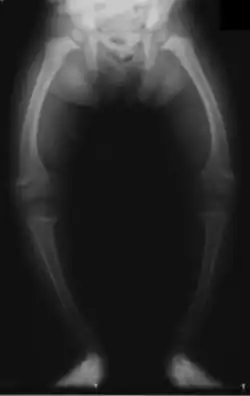

Fetuses and children who do not get enough vitamin D can result in "growth retardation and skeletal deformities."[23]